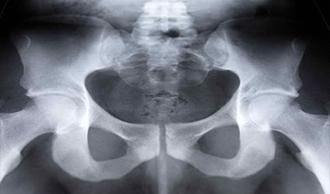

Imagen lesiones lesOsea artritis cadera

La artritis es la inflamación de las articulaciones. Es un término genérico que engloba diversas patologías articulares; el tipo más común de artritis de cadera es la osteoartritis (OA) o artrosis.

La superficie articular superior del fémur se articula con la pelvis en la articulación de la cadera están cubiertas de cartílago. Eeste cartílago hace posible que los extremos de los huesos se muevan el uno contra el otro con suavidad. Si se padece osteoartritis, el cartílago se va erosionando gradualmente y se hace más delgado.